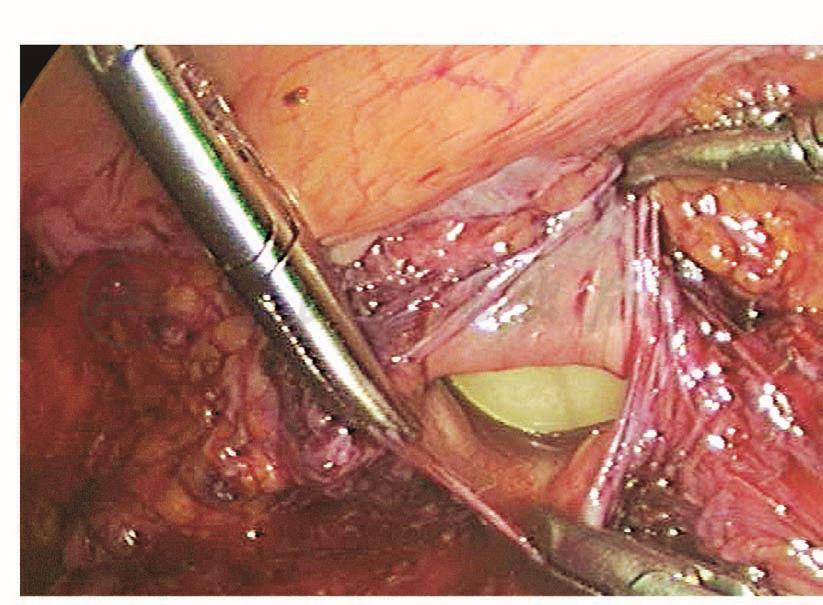

如果术中无法确认输尿管是否损伤,可以考虑在结束手术前进行膀胱镜检查,观察输尿管出口的喷尿情况。膀胱镜下先找到膀胱黏膜,在膀胱底部找到突出的部位,此处即为膀胱三角区,输尿管出口位于其两侧。有时候输尿管蠕动的间隔比较长,必要时可以静脉注射呋塞米20mg,促进输尿管蠕动、喷尿。如果观察到两侧输尿管出口正常蠕动并有喷尿,说明输尿管没有断裂性损伤,但不能排除热损伤(图117~图120)。

图117 膀胱三角区

图118 左侧输尿管出口

图119 右侧输尿管出口

图120 输尿管出口喷尿